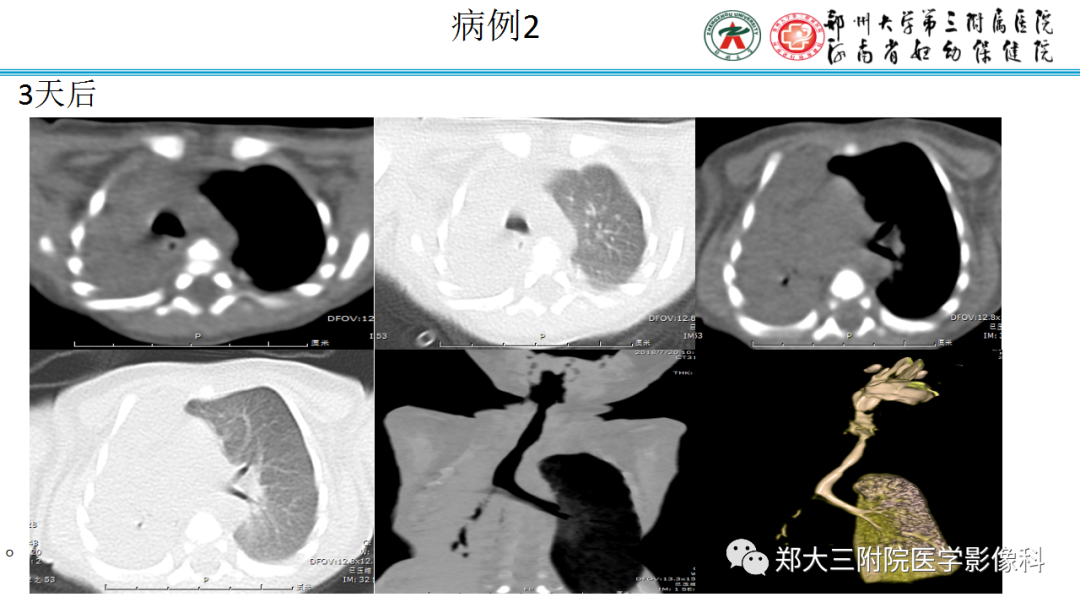

男,41岁,临床发现双肾结石10年。

纵隔大细胞神经内分泌癌1例CT影像

纵隔大细胞神经内分泌癌1例CT影像  张力性纵隔气肿影像表现及严重度分级

张力性纵隔气肿影像表现及严重度分级  迅速增大的肺部结节,首先考虑良性,确诊需要肺穿

迅速增大的肺部结节,首先考虑良性,确诊需要肺穿  肺隔离症:易误诊为肺癌的占位性病变,肺穿刺禁忌!

肺隔离症:易误诊为肺癌的占位性病变,肺穿刺禁忌!  肺段与肺内管道应用解剖